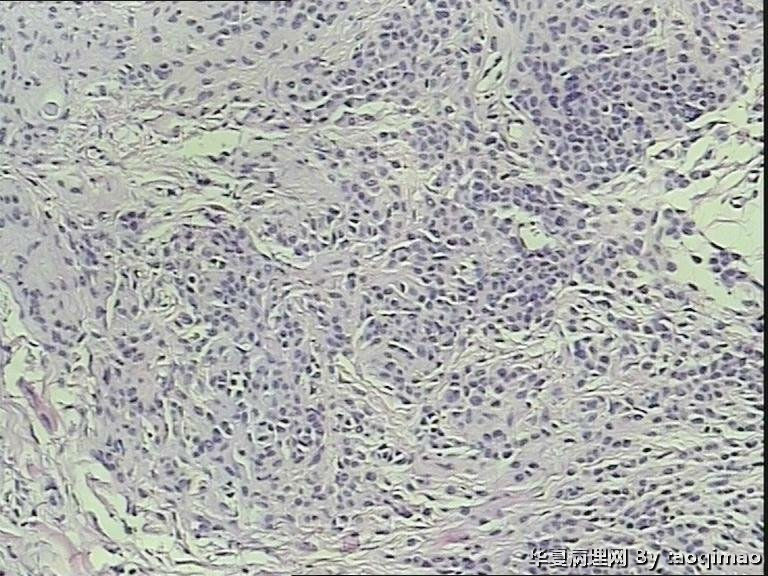

两例头皮肿物有差别么

34岁女,头皮肿物,带皮组织一块1x1,皮瓣上可见一灰白结节大小0.6x0.6,皮瓣大小1x0.4 面灰白质软。

门诊患者这一例没有其它更多信息

第一:皮内痣 第二:皮内痣并表皮囊肿

这个患者女,24岁,右颞部头皮肿物 24年,带皮的组织一块1.7x1x1,突出于皮肤表面,灰白色肿物,剖面实性灰白,请各位老师给帮忙诊断一下,这两个病例是同一个诊断么

没差别

皮内痣。

都考虑皮内痣。

但第一例处于退化期了,当然,这没必要写到报告上。

都要考虑皮内痣。实在有差别就是第2例上有表皮囊肿,容易伴发。

皮内痣,第2例伴表皮囊肿,1处于退化期,倒是该学学

第二例合并的有个小的表皮样囊肿,或说粟丘疹。

灰白色,我想是由于有的皮内痣本身没有太多色素吧,不少皮内痣是皮色的。你的俩病例,片子里都没啥见到色素,应该可以解释了吧。

头皮皮内痣常呈皮赘样,质软有蒂,很多时候退化后呈正常肤色,切片中常有成熟的脂肪细胞,临床很容易误诊,诊断皮内痣应该没有问题的!